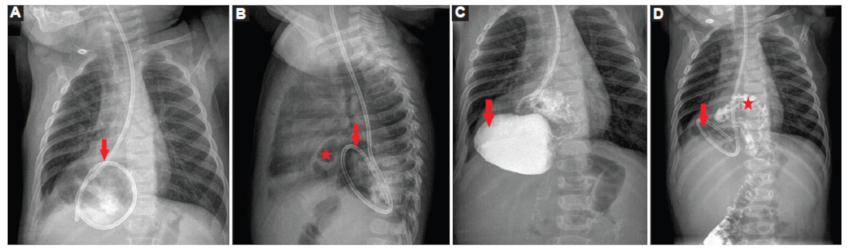

Reconsultó tras 20 días por reaparición de vómitos hemáticos y pérdida ponderal. En la exploración física destacó una hipoventilación en base pulmonar derecha, sin signos de dificultad respiratoria y afebril, con analítica sanguínea anodina. Se realizó una radiografía de tórax, objetivando una imagen en base pulmonar derecha compatible con hernia diafragmática (Fig. 1), hallazgo que permitió la realización de pruebas confirmatorias (Figs. 2 y 3) y un manejo precoz y adecuado del caso.

Se realizó intervención quirúrgica laparoscópica objetivando gran hernia a través de hiato esofágico que incluía colon transverso, estómago completo incluido el píloro y primera porción duodenal en situación invertida, sin signos de estrangulación. Se realizó reducción, resección parcial del saco herniario, cierre de los pilares, fijación de esófago a diafragma y funduplicatura de Nissen, previniendo la aparición de reflujo gastroesofágico posquirúrgico, presentando evolución posterior satisfactoria sin complicaciones.

La confirmación diagnóstica debe realizarse con un estudio radiológico esófago-gastro-duodenal con contraste. La realización de tomografía computada (TC) habitualmente debe reservarse para casos donde existan dudas diagnósticas o para precisar la posición anatómica3.